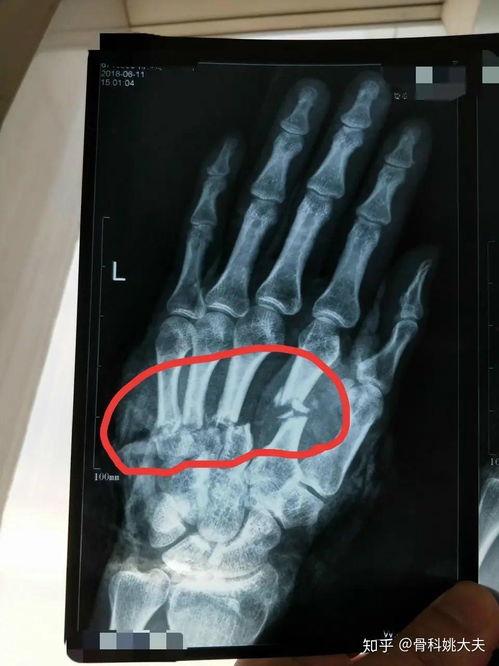

手骨骨折图片,影像学诊断与治疗策略 最近是不是不小心摔了一跤,手骨骨折了?别担心,今天就来给你详细介绍一下手骨骨折的情况,让你对它有个全面的认识。咱们就从那些让人看了都心疼的手骨骨折图片开始吧!一、手骨骨折的常见类型首先,你得知道手骨骨... admin 爆料求搞 2026-02-22 7 0